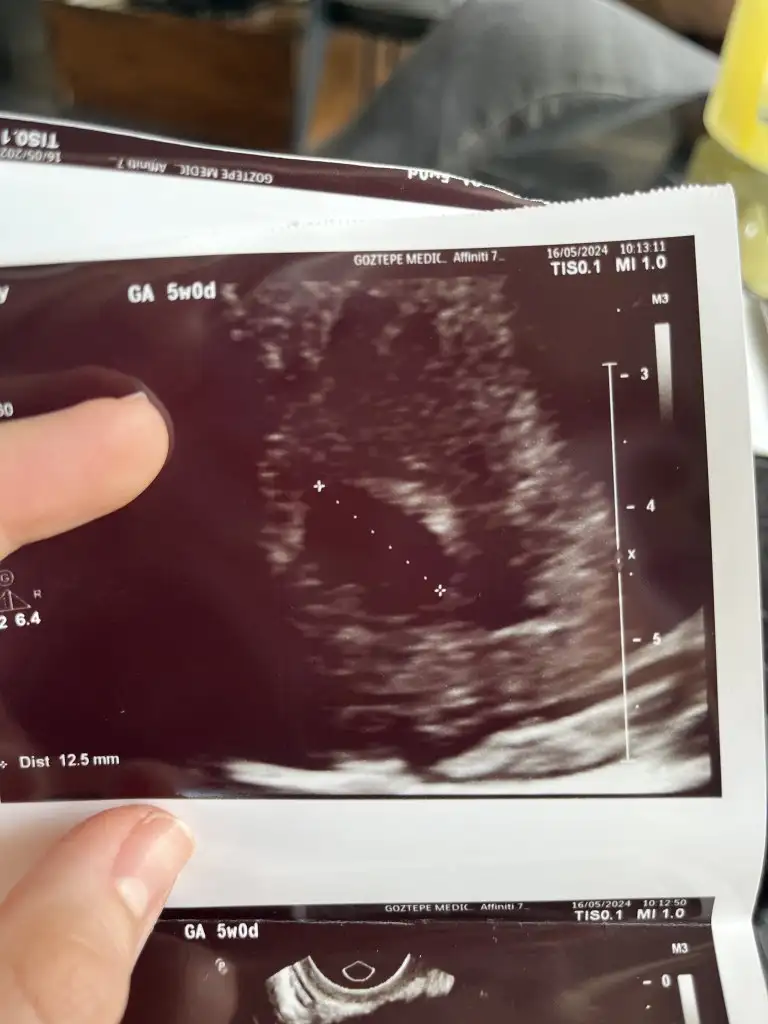

Kızlar selam, ben de dün doktora gittim, sata göre 5+6 görünüyordu ama doktor tam 5 haftalık dedi. Geç döllenme mi olmuş oluyor bu durumda? Görüntü de böyle. ♥️ umarım hepimiz için sağlıklı bir süreç ilerle ♥️

Eklentiler

• IMG_4593.webp

IMG_4593.webp

37,3 KB · Görüntüleme: 98